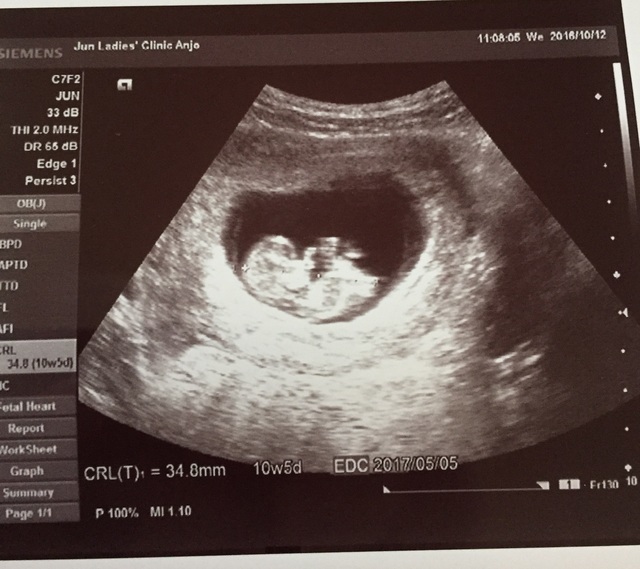

10週5日(10w5d・女の子)|さッちゃん さん(27歳)

エコー写真撮影時のエピソード:

妊娠して初めて人の形がわかったエコー写真です。 初めての妊娠で毎日不安でしたし、悪阻が酷く立っているのも大変でした。

このエコー写真をもらった時、やっとお腹にこの子がいるんだなって実感が湧いたと共にすごく愛おしく思いました。

この時の旦那は、父親になる実感がまだ無かったのが懐かしく感じます。 今の幸せがあるのは、この子のおかげだなって思いました。